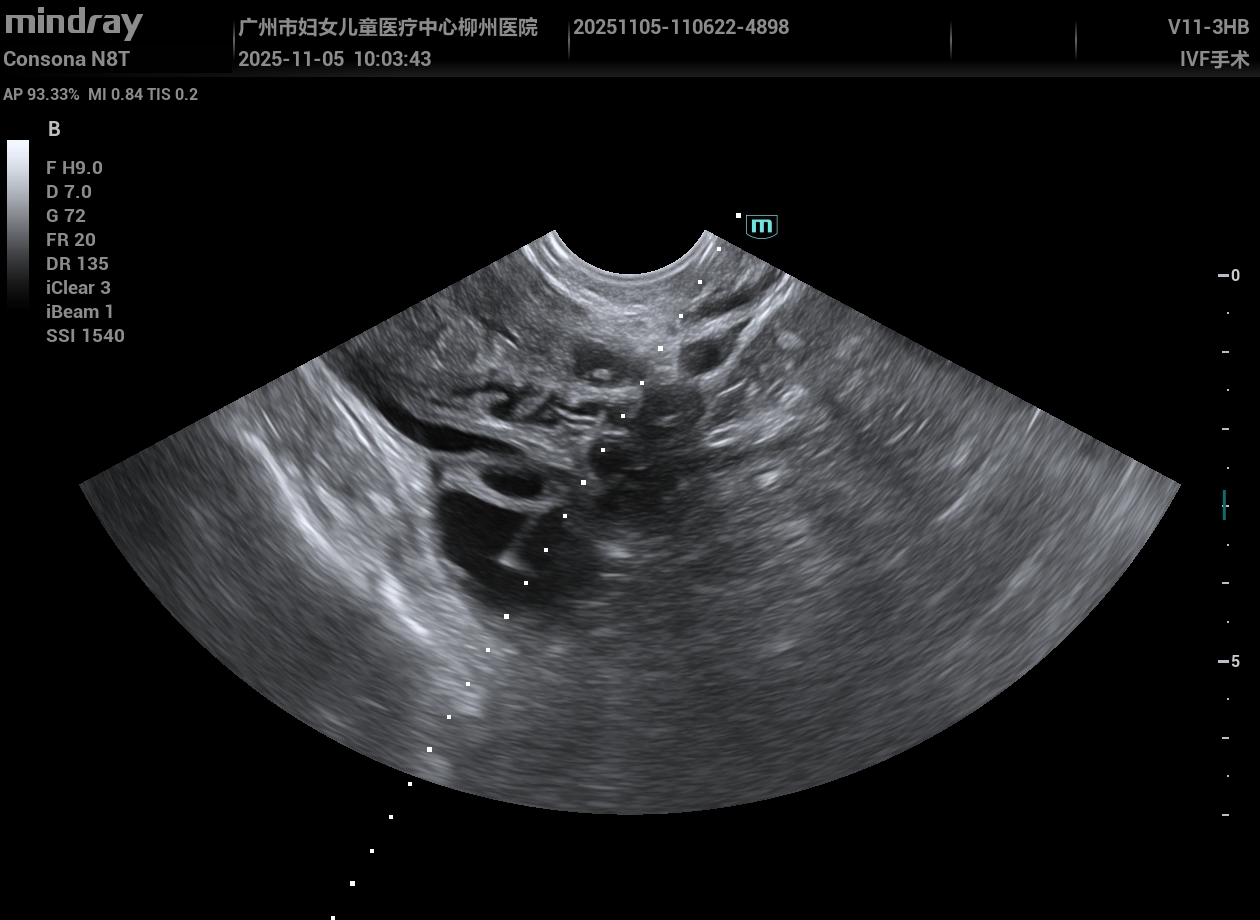

实例,超声可视化穿刺取卵细胞视频,弯把探头,操作方便快捷。